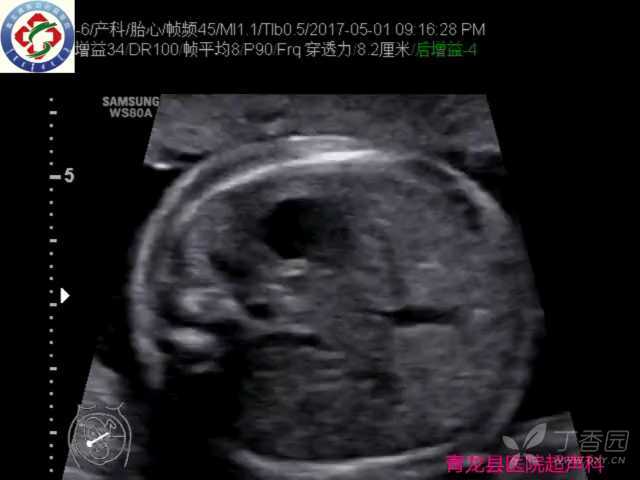

胎儿“U”形血管环一例

孕24周胎儿心脏超声检查所见:

大动脉:主动脉瓣开闭无明显异常,升主动脉、主动脉弓及降主动脉连续性好,主动脉弓走行于气管右侧,与左位动脉导管形成U形环,左锁骨下动脉起自于降主动脉,于气管食管后方向左肩部走行;

CDFI、 DOPPLER检查:可见迷走左锁骨下动脉内血流信号。

①在3VT切面表现为环绕气管周围的“U”形或“C”形血管环,彩色多普勒血流则更加清楚地显示“U”或“C”形彩环,此“U”形为右位主动脉弓、迷走左锁骨下动脉、左位动脉导管环绕气管形成,“U”形血管环的另一侧为心底结构,所以在气管周围形成了一个“三面环水一面依山”的封闭环形结构,此为完全血管环,这种情况还见于左位主动脉弓伴发右锁骨下动脉迷走、右位动脉导管。“C”形为右位主动脉弓,迷走左锁骨下动脉环绕气管形成,动脉导管为右位动脉导管。